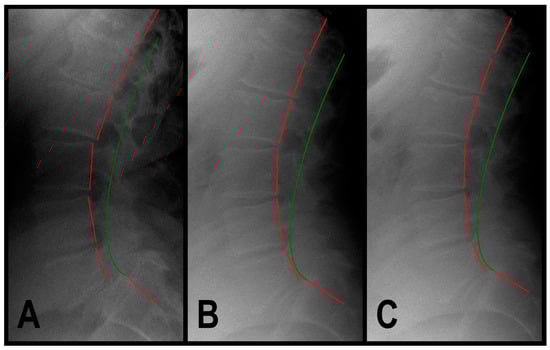

3.1.3. Patient 3

| ARA L1-L5 (°) | −40 | −51.2 | −45.2 | −45.4 | |

| Tz L5-S1 (mm) | 0 | 13.8 | 4.2 | 4.3 | |